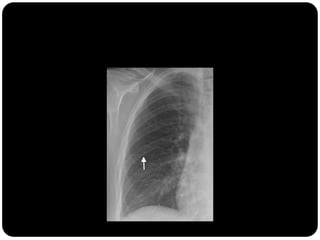

O que está anormal?

Vias aéreas

Amiloidose

traqueobrônquica

Depósitos de

amilóides de maneira

circunferencial

causando

estreitamento

irregular da traquéia;

Pneumonia e

atelectasia frequente;

Biópsia – vermelho

Congo